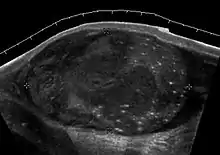

Rhabdomyosarcoma (a) Longitudinal section (composite image) of high resolution ultrasound of a 14-year-old boy shows a well defined hypoechoic extratesticular mass is found in the left scrotum, hydrocele is also present. (b) Color Doppler ultrasound shows that the mass is hypervascular.

Rhabdomyosarcoma is the most common tumor of the lower genitourinary tract in children in the first two decades, it may develop anywhere in the body, and 4% occur in the paratesticular region which carries a better outcome than lesions elsewhere in the genitourinary tract. Clinically, the patient usually presents with non-specific complaints of a unilateral, painless intrascrotal swelling not associated with fever.

Transillumination test is positive when a hydrocele is present, often resulting in a misdiagnosis of epididymitis, which is more commonly associated with hydrocele. The ultrasound findings of paratesticular rhabdomyosarcoma are variable. It usually presents as an echo-poor mass [Fig. 11a] with or without hydrocele. With color Doppler sonography these tumors are generally hypervascular.